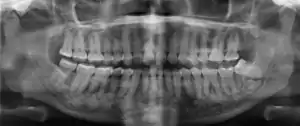

Cemento-osseous dysplasia (COD) is a benign condition of the jaws that may arise from the fibroblasts of the periodontal ligaments. It is most common in African-American females. The three types are periapical cemental dysplasia (common in those of African descent), focal cemento-osseous dysplasia (Caucasians), and florid cemento-osseous dysplasia (African descent). Periapical occurs most commonly in the mandibular anterior teeth while focal appears predominantly in the mandibular posterior teeth and florid in both maxilla and mandible in multiple quadrants.

| Diagnostic method | X-ray, CBCT scan, vitality testing of teeth |

Diagnosis is important so that the treating doctor does not confuse it for another periapical disease such as rarefying osteitis or condensing osteitis. Incorrect diagnosis could lead to unnecessary root canal treatments. It can be diagnosed by radiographic appearance. Confirming the tooth is vital, as is noting the demographic (African American females).